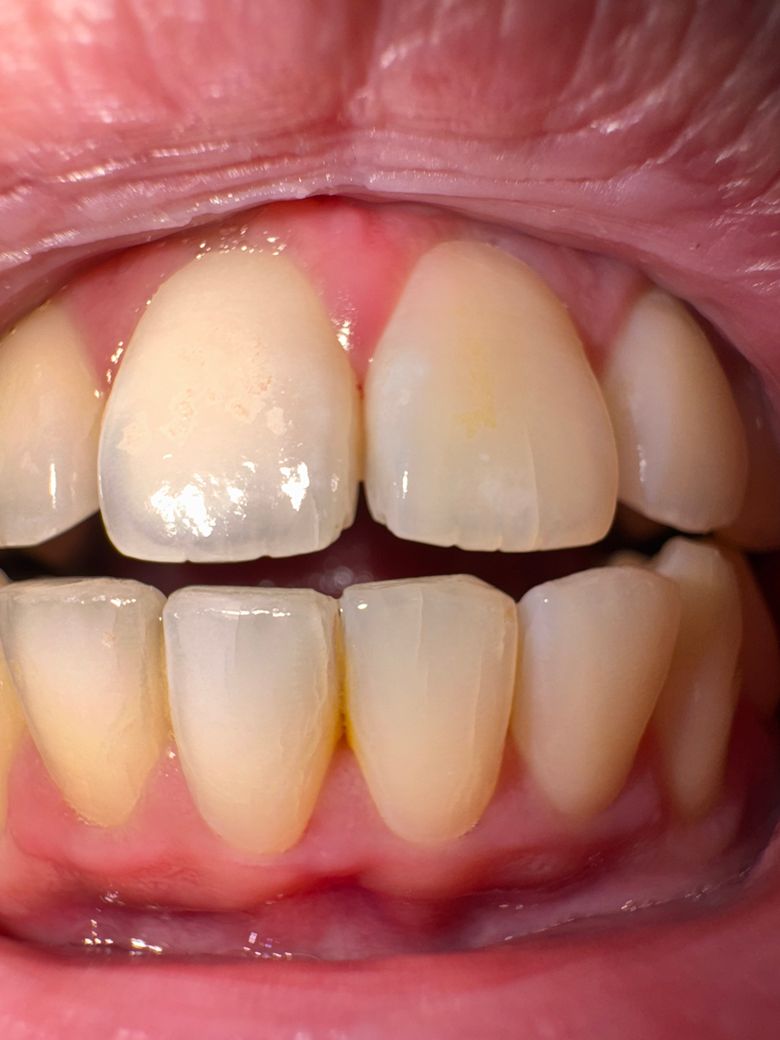

아프거나 불편하진 않은데 앞니에 금이 보여요

평상시엔 몰랐는데 플래시를 켜고 보니까 앞니에 금?처럼 선이 여러개 보여요. 아프거나 불편하진 않습니다.

• 1번 째 사진

앞니의 경우 교합이 좋지 않으면 표면에 실금이 가는경우가 있습니다. 증상이 없다면 조심히 사용하시면 크게 문제가 되진 않습니다.

치아에 과도한 힘이 가해지게 되면 치아에 금이 갈 수 있습니다. 금이 갔다는 것은 그만큼 치아에 무리가 가해졌다는 것이기 때문에 해당 치아에 힘이 과도하게 가해지지 않도록 주의를 해주는 것이 좋습니다. 불편감이 있다면 치료를 하는 것이 좋지만 불편감이 없다면 관리를 하면서 지켜볼 수 있습니다.

앞니를 사용하다보면 저렇게 잔 금이 생기기도 합니다. 저렇게 작은 금(craze line)이 생기는 분들이 굉장히 많고

아직 너무 걱정하실 단계도 아니고 저런 상태로 평생을 가시는 분들도 많으니 너무 걱정하지 마시고 앞니로 너무 딱딱하거나 질긴것을 먹는 행동만 줄여주시면 되겠습니다.

현재로선 증상이 없는 치아 표면 균열이기 때문에 특별히 조치할 것도 없고 치과에서 해줄 수 있는 것도 없습니다. 조심해서 잘 쓰시는 수 밖에 없습니다. 앞니로는 특히 음식을 씹지 않도록 주의하셔야 합니다.